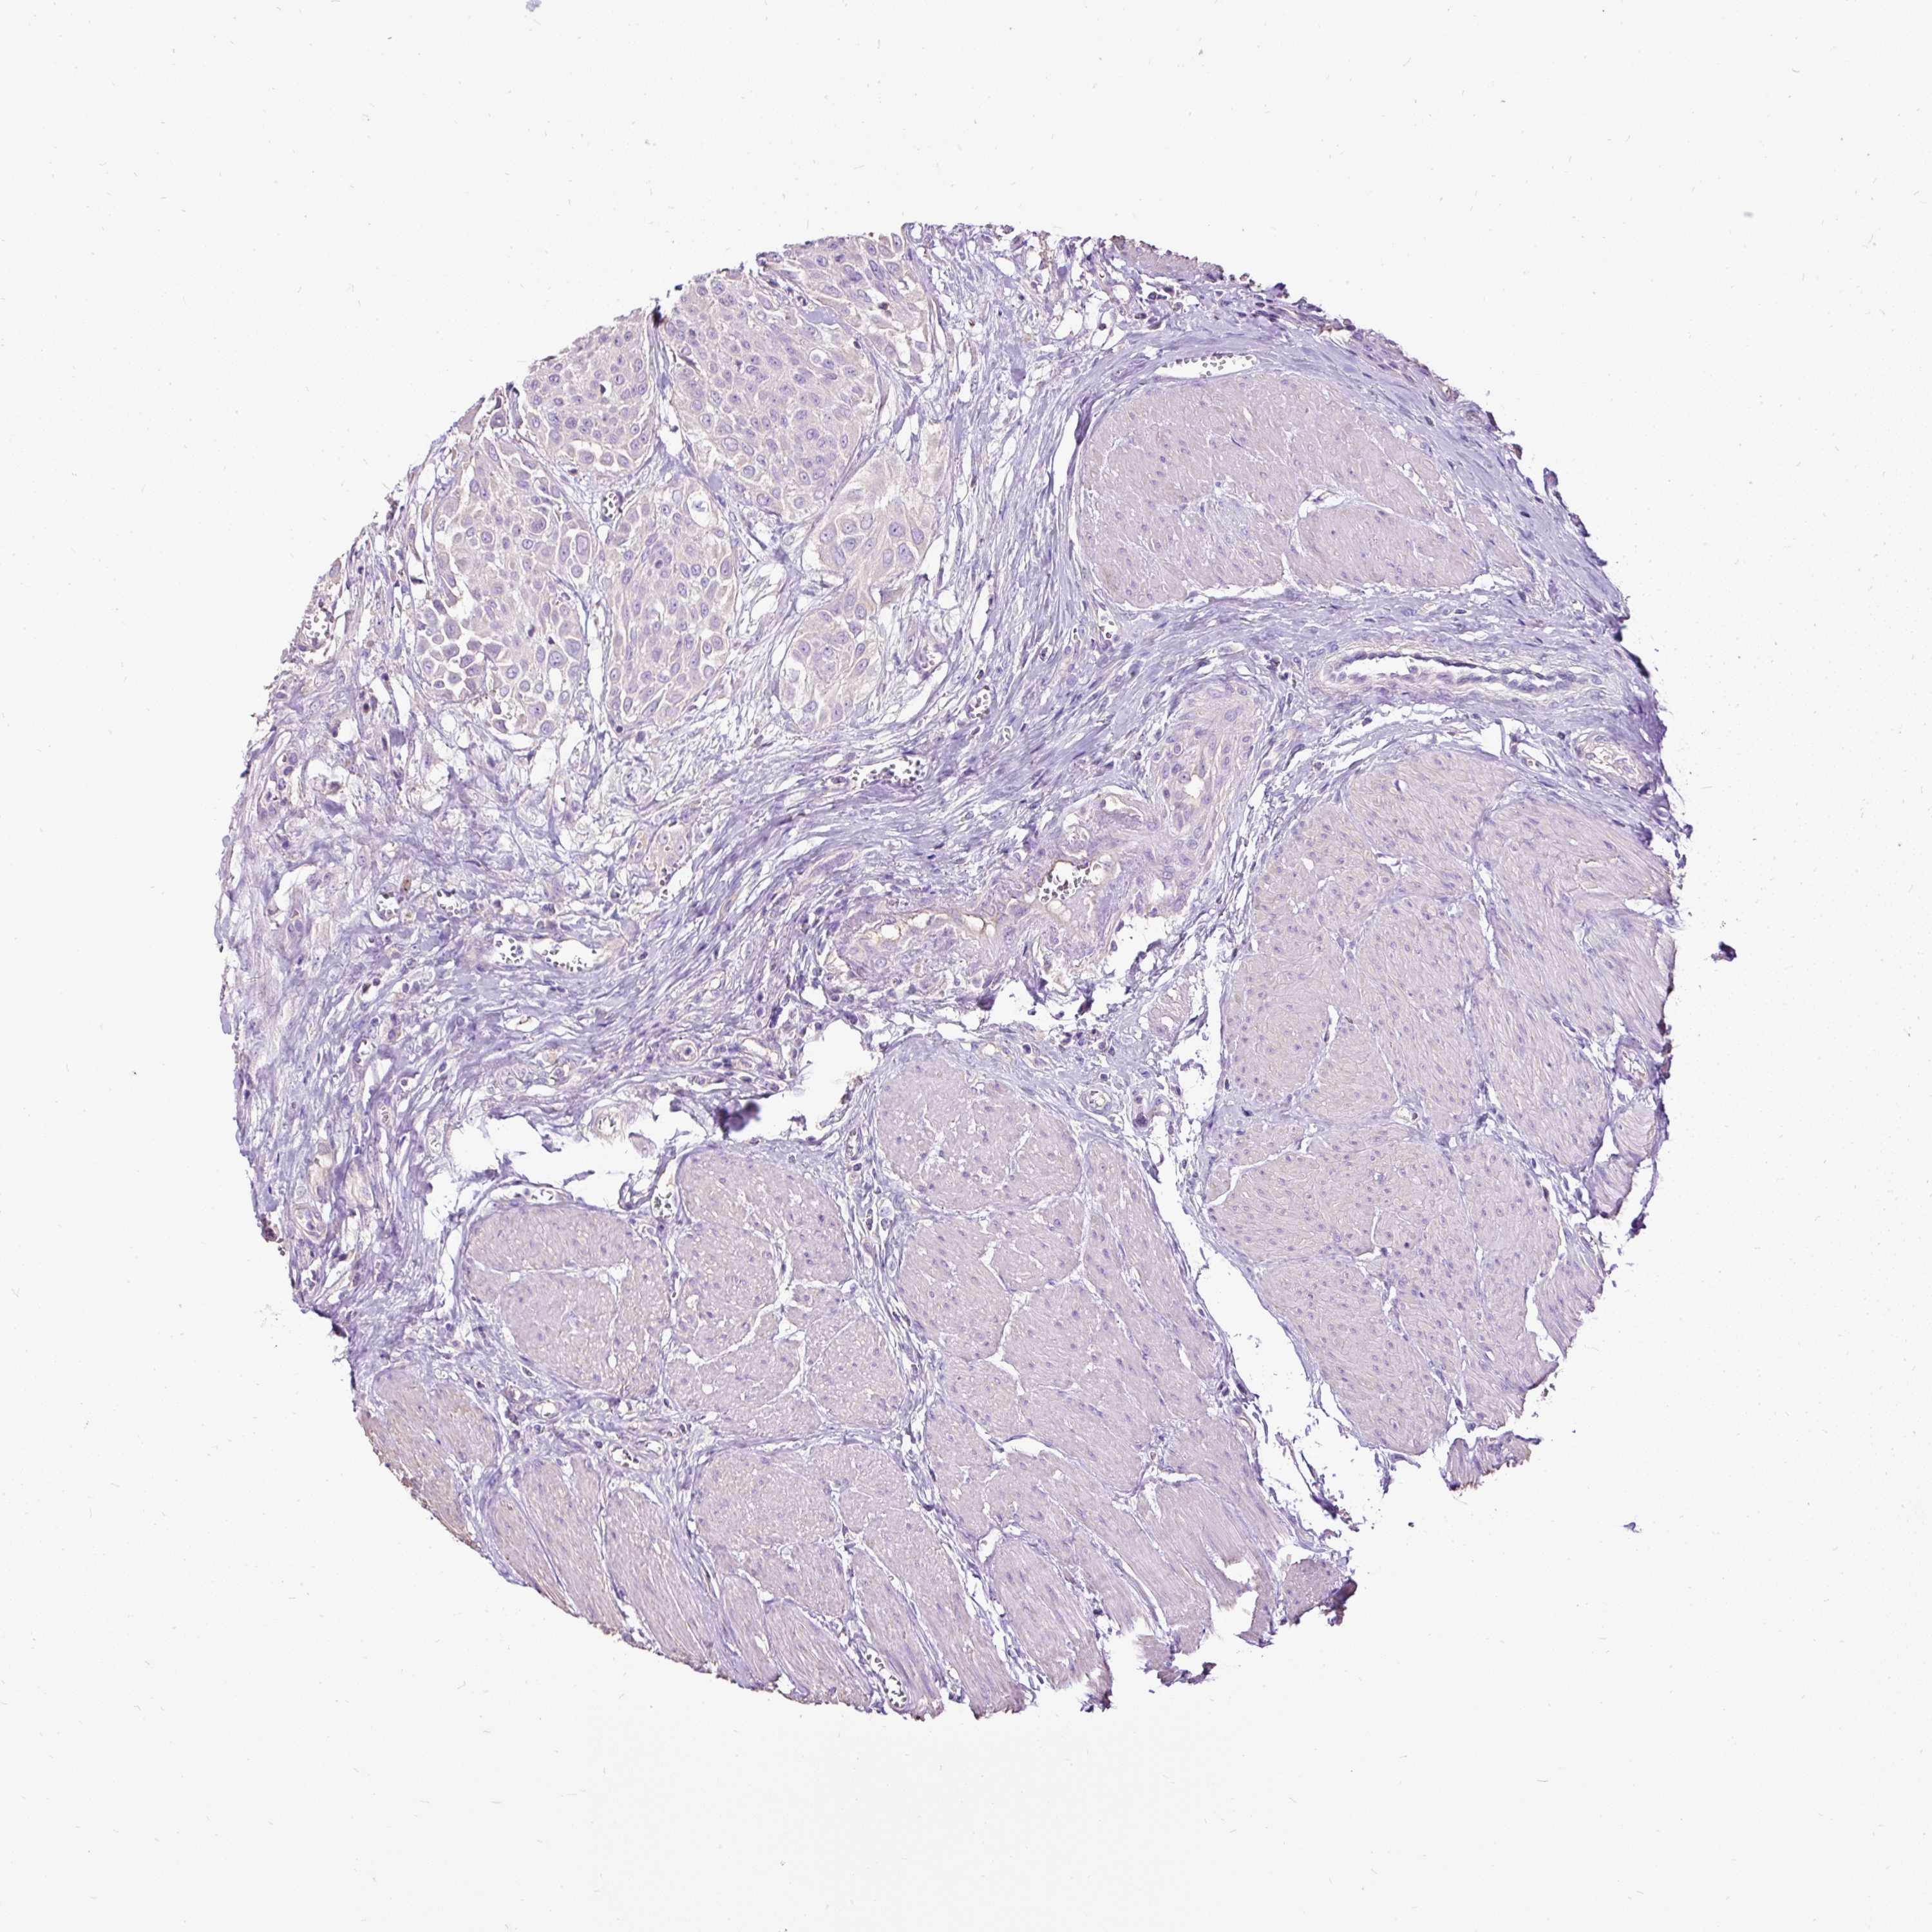

UROTHELIAL CANCER - Protein expressioni

A mouse-over function shows sample information and annotation data. Click on an image to view it in a full screen mode. Samples can be filtered based on level of antibody staining by selecting one or several of the following categories: high, medium, low and not detected. The assay and annotation is described here.

Note that samples used for immunohistochemistry by the Human Protein Atlas do not correspond to samples in the TCGA dataset.

Antibody stainingi

Antibody staining in the annotated cell types in the current human tissue is reported as not detected, low, medium, or high, based on conventional immunohistochemistry profiling in selected tissues. This score is based on the combination of the staining intensity and fraction of stained cells.

Each image is clickable and will lead to virtual microscopy that enables deeper exploration of all samples and also displays staining intensity scores, fraction scores and subcellular localization as well as patient and tissue information for each sample.

Antibody HPA051692

Antibody HPA053492

Urothelial carcinoma, High grade

Urothelial carcinoma, Low grade

Urothelial carcinoma, NOS